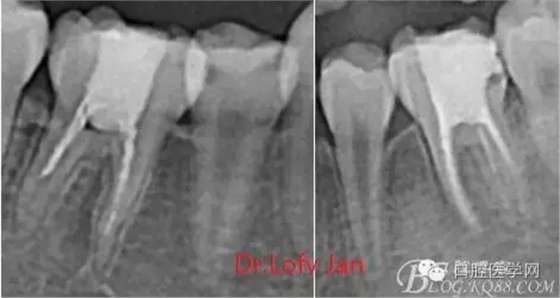

曲面斷層片在未試尖根管治療中的病例整理

前言:自己做的一些曲面斷層片在未試尖根管治療中的病例整理,發(fā)現(xiàn)問題很多包括自身的,技術(shù)的,還有設(shè)備的問題,予以總結(jié)整理并期待進(jìn)一步提高。

根管治療術(shù)是牙體牙髓疾病治療中最復(fù)雜和最關(guān)鍵的治療項(xiàng)目。根管充填材料抵達(dá)根尖、并能嚴(yán)密堵塞根尖孔,是確保根管治療效果的關(guān)鍵指標(biāo)。為了保證根管充填到位,醫(yī)生需要在術(shù)前照牙片以了解牙根根管的數(shù)量、彎曲程度和長(zhǎng)度,在術(shù)中有時(shí)需要插針照牙片來精確測(cè)量根管長(zhǎng)度,術(shù)后必須照牙片以確定是否根管充填到位,如果欠填或超填,就需要重新充填、重新照牙片確認(rèn),直到根管充填到位。所以,在患者接受根管治療時(shí)有時(shí)會(huì)反復(fù)照牙片。

病例分析:曲面斷層片在x線輔助診斷與檢查中目前大多數(shù)文獻(xiàn)和著作都建議只能作為初診拍片檢查手段,不能作為終末疾病的確診與手術(shù)療效的評(píng)價(jià)指標(biāo),臨床大部分中小型門診都因?yàn)樵O(shè)備不齊全導(dǎo)致信息偏差很大。